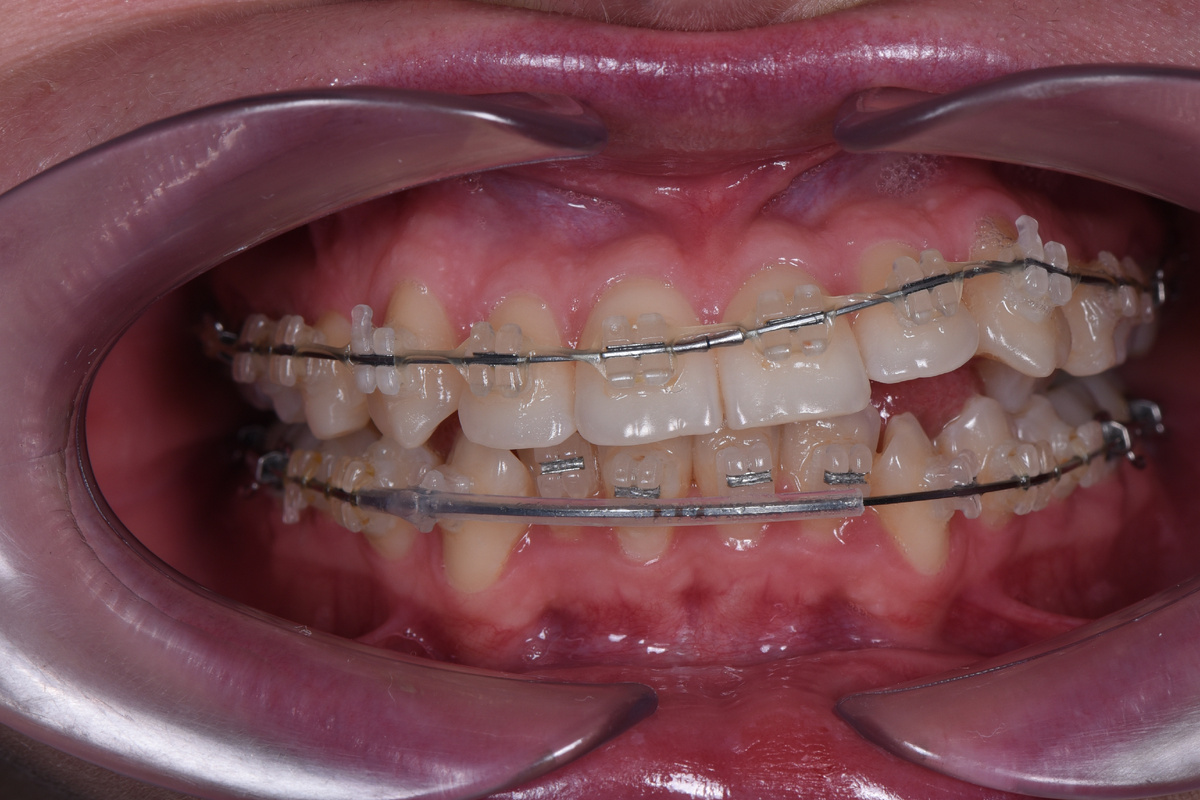

Девушка пришла на прием, — и вот, что мы увидели👇

При обращении к нам зубы пациентки выглядели так

Основная сложность этого случая заключается в скученности зубов: для всех зубов просто не хватает места. Из-за этого и возникли проблемы с лечением. В частности, из-за большого объема зубов на верхней челюсти даже не смог выпрямиться прогиб дуги. Левая сторона челюсти не опустилась в области клыка и резца.

Внизу нижние резцы не включены в дугу — если бы их подвязали к дуге, они бы очень сильно вышли вперед.